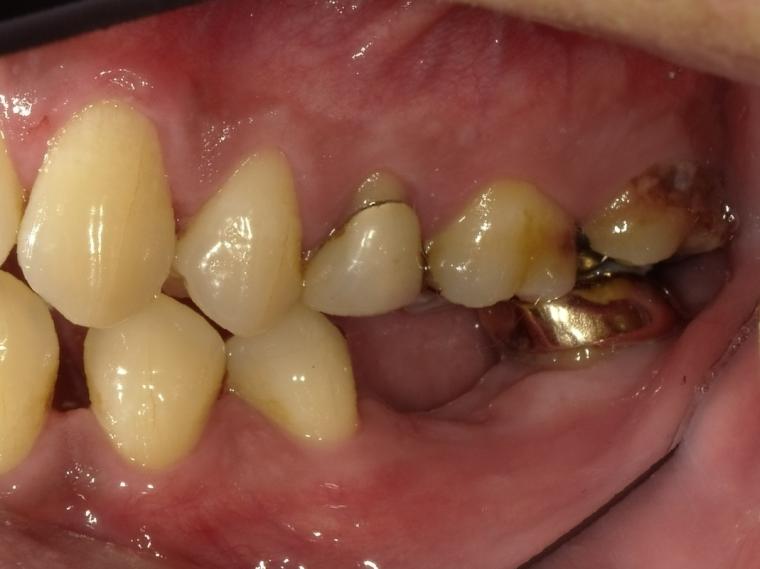

BEFORE

44歳男性

/下顎1本欠損/インプラント埋込手術

他院で左下第一大臼歯を治療していましたが、治療を中断してしまい、状態が悪化、抜歯になった患者さんです。

インプラントでの治療を希望されて当院へご来院されました。